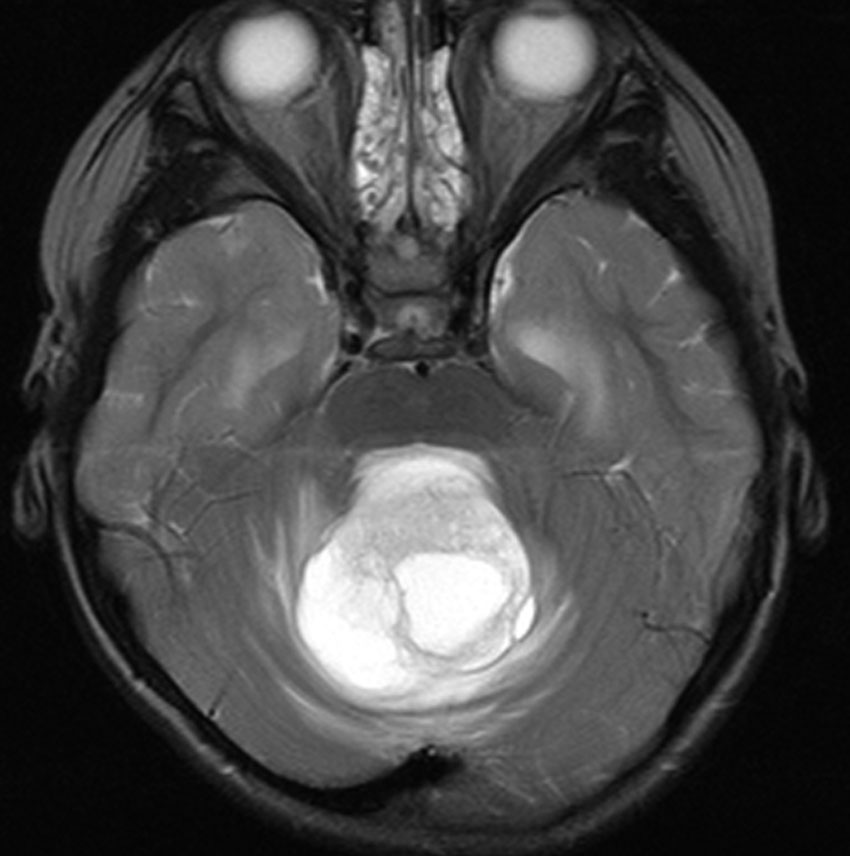

左は脳幹部腫瘍(退形成性神経節膠腫),右は小脳腫瘍(毛様細胞性星細胞腫)です。どちらも第4脳室を埋め尽くすように発育しています。これらはどちら側から発生したかが明瞭な例ですが,第4脳室腫瘍の中には脳幹部からか小脳からか解らないものもあります。でも多くは小脳側からです。脳幹部側からで注意しなければならないのは上衣腫と血管芽腫です。